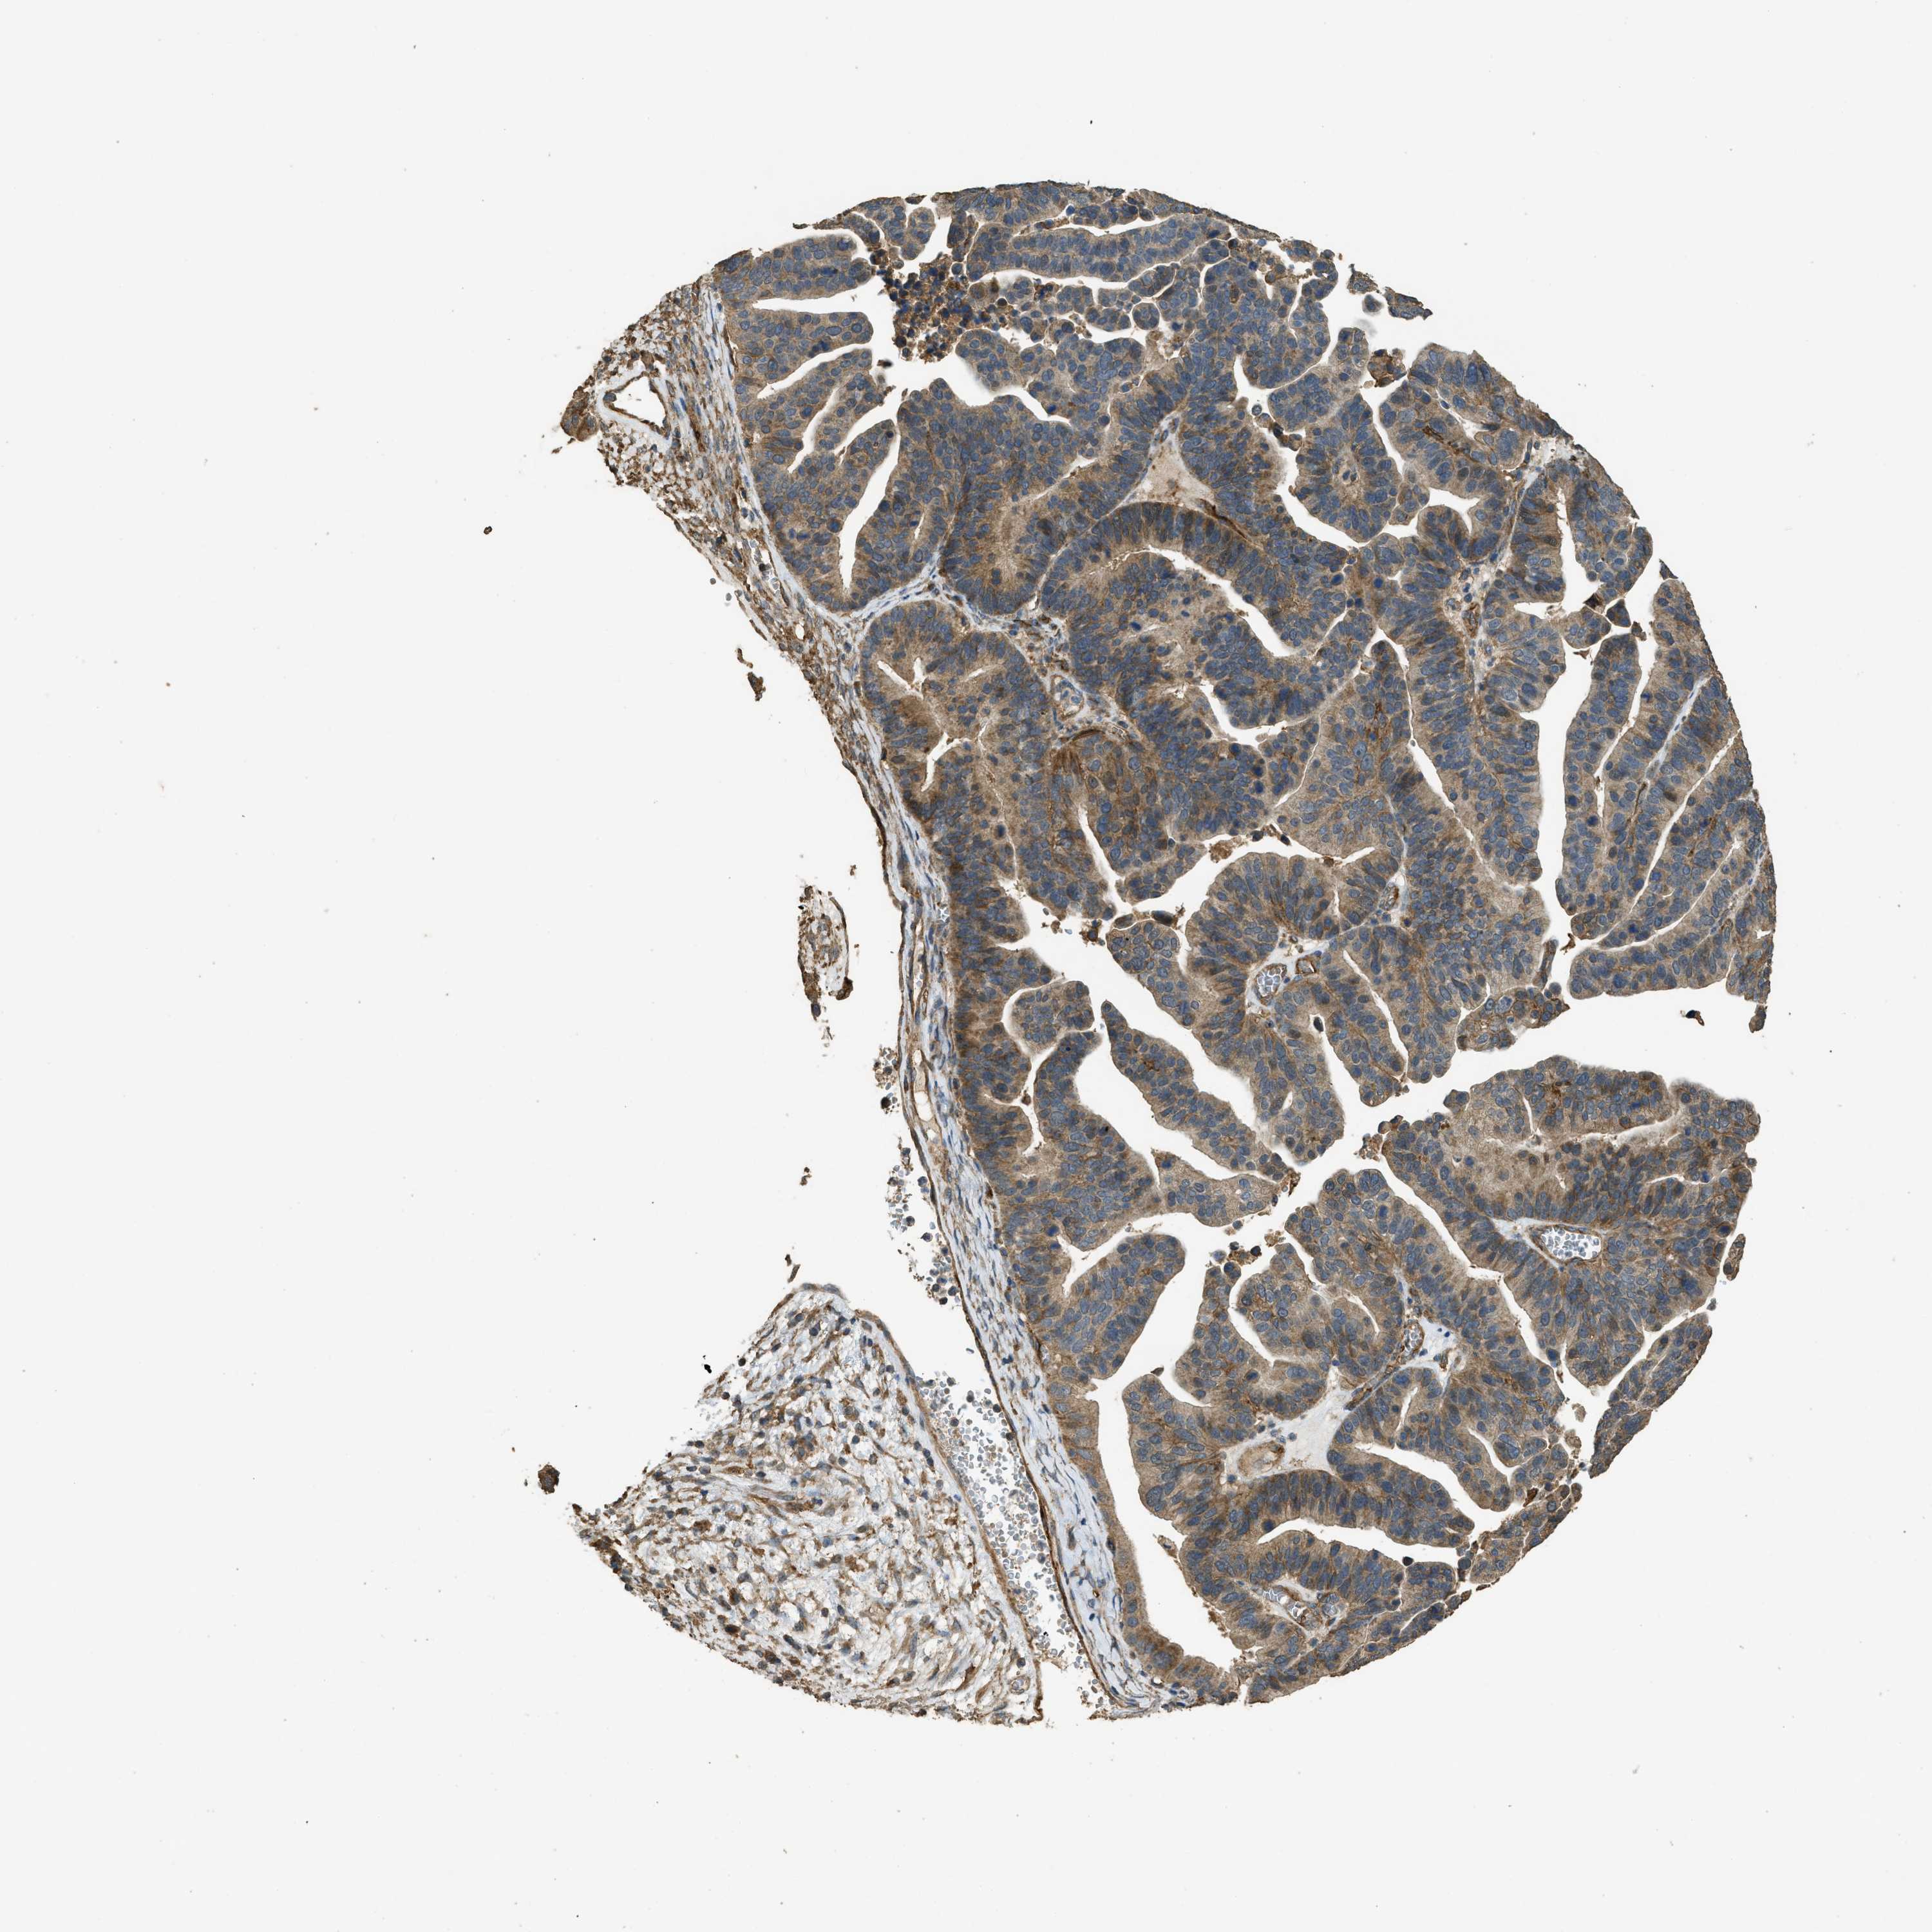

OVARIAN CANCER - Protein expressioni

A mouse-over function shows sample information and annotation data. Click on an image to view it in a full screen mode. Samples can be filtered based on level of antibody staining by selecting one or several of the following categories: high, medium, low and not detected. The assay and annotation is described here.

Note that samples used for immunohistochemistry by the Human Protein Atlas do not correspond to samples in the TCGA dataset.

Antibody stainingi

Antibody staining in the annotated cell types in the current human tissue is reported as not detected, low, medium, or high, based on conventional immunohistochemistry profiling in selected tissues. This score is based on the combination of the staining intensity and fraction of stained cells.

Each image is clickable and will lead to virtual microscopy that enables deeper exploration of all samples and also displays staining intensity scores, fraction scores and subcellular localization as well as patient and tissue information for each sample.

Antibody HPA009285

Antibody HPA017139

Antibody CAB017826

Cystadenocarcinoma, serous, NOS

Carcinoma, endometroid

Cystadenocarcinoma, mucinous, NOS

Carcinoma, NOS